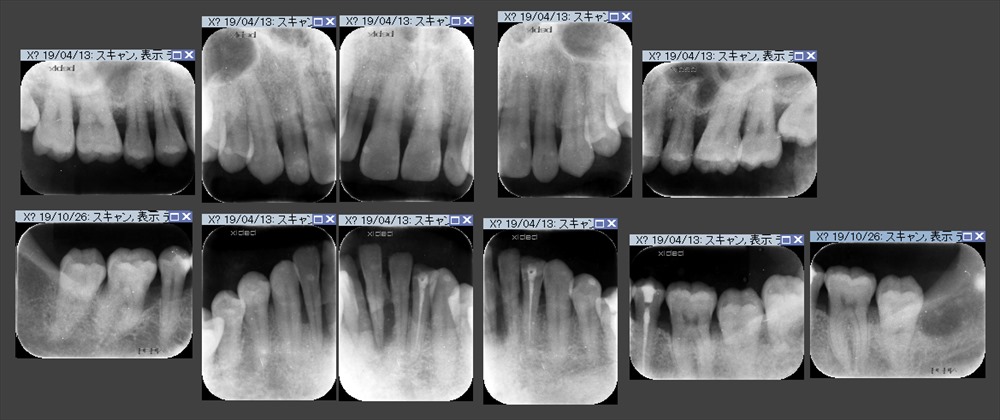

レントゲン

骨の量も全額的に少なく、下の前歯は抜けていました。

右下の6番 膿が出ていました。。。

ここは垂直的に骨が無くなっていました。ポケットは7mm。

歯周初期治療(MINST)を徹底的に行いました。下記写真は初期治療後のデータです。

ここまで回復しました。右下6番以外はすべて4mm以内に落ち着きました。